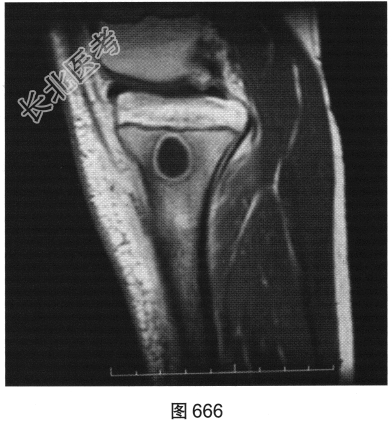

- 多项选择题3.[提示]患者行右小腿X线平片及CT、MRI检查,见图664~图666。该病最可能的诊断是( )

A、Brodie骨脓肿

- 多项选择题4.Brodie骨脓肿的诊断依据是( )

A、MRI囊内为液性信号并见环状等信号薄壁,周围见水肿区

B、CT示囊样骨质破坏,边缘有硬化

C、患者为青少年

D、X线见类圆形骨质破坏,边界清楚伴边缘骨质硬化

E、发热、患肢疼痛、肿胀等典型症状

F、起病较急